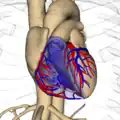

Heart and its blood vessels.

Heart and its blood vessels. -